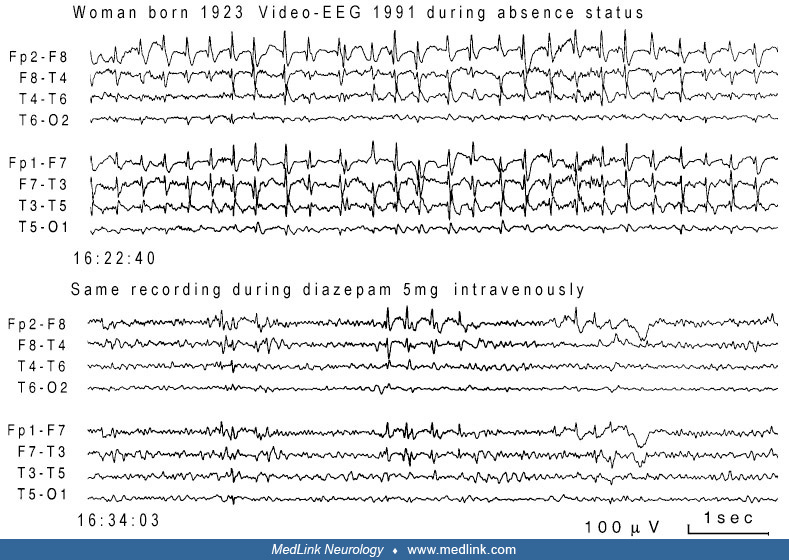

From www.medlink.com

Absence status epilepticus (ASE) MedLink Neurology What Are Status Epilepticus This is a medical emergency that may lead to permanent brain damage or. Status epilepticus is a medical and neurologic emergency that requires prompt evaluation and treatment. It is a medical emergency and requires. Status epilepticus is when a seizure lasts for 5 minutes or more or when a person does not regain consciousness between seizures. “status epilepticus” literally means. What Are Status Epilepticus.